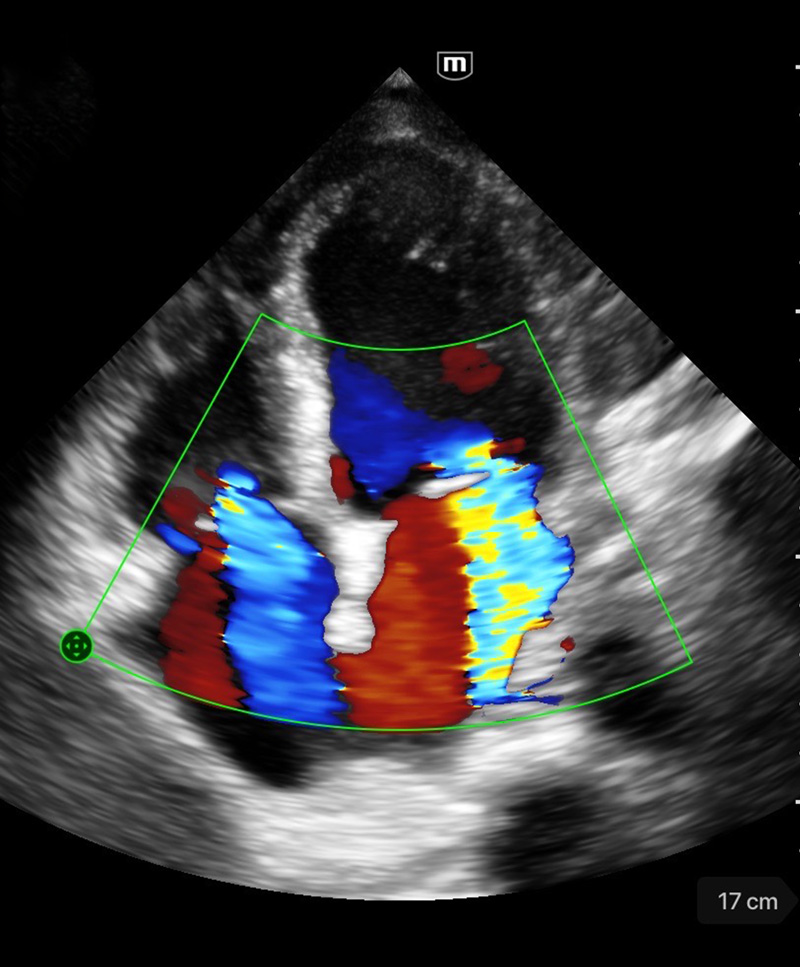

Професионално качество на диагностичните изображения

Различни режими на изображението

Множество режими за сканиране

Color mode

Клинични снимки